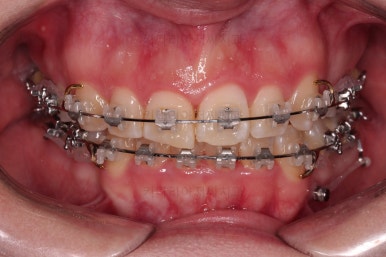

동래교정치과 마무리 사진입니다.

종료 이후에는 어금니의 기존 크라운 보철이 오래되고 탈이나서 재보철을 해주었습니다.

앞니는 비뚠채로 장기간 마모가 되어온 터라 형태가 부적절하긴 한데요.

보철로 마무리하기 보다는 최대한 자연스럽게 시리지 않는 선에서 다듬어 드리고 마무리를 했습니다.